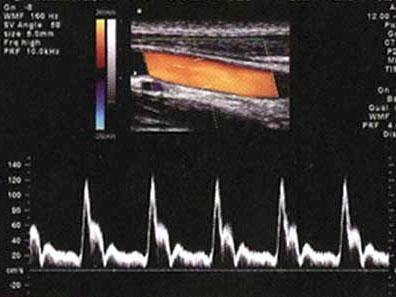

问题 某患者血管超声彩色多谱勒检查,如图所示,诊断为?(?)

选项 A.正常动脉层流频谱 B.正常静脉层流频谱 C.异常动脉频谱 D.异常静脉频谱 E.以上都不是

答案 A